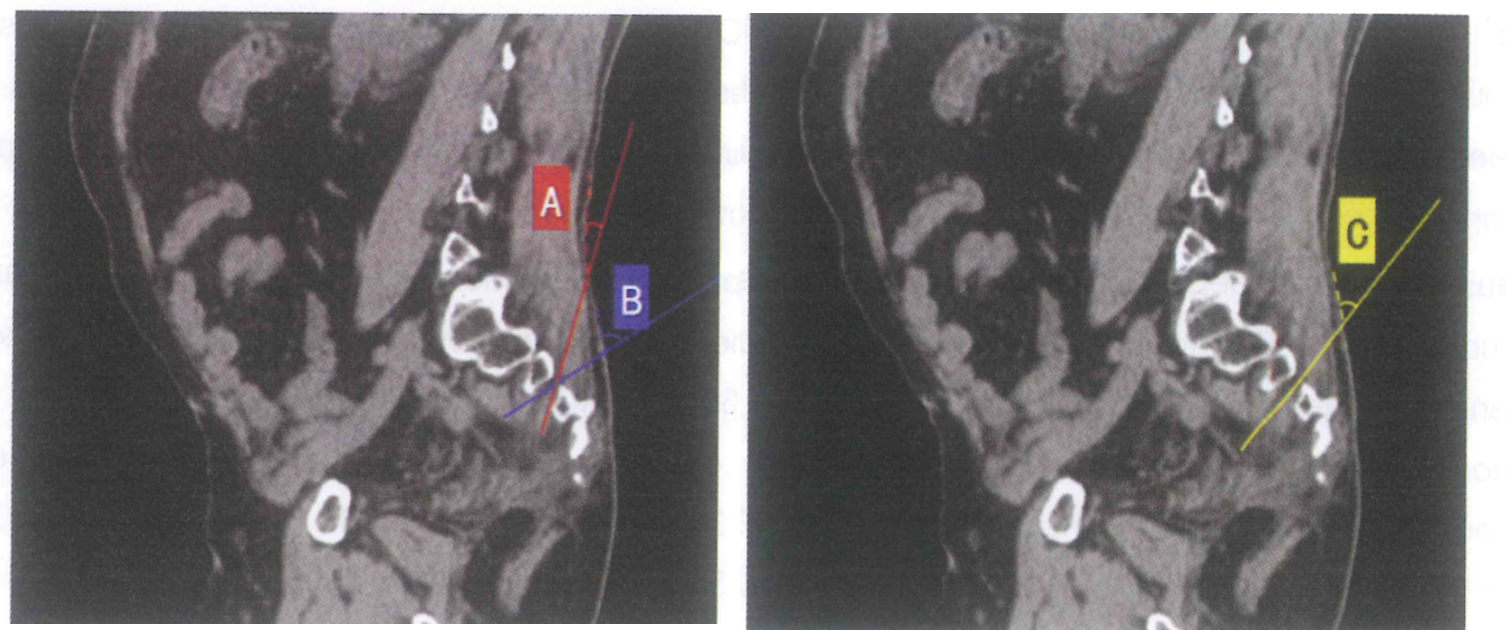

Figure 6. Plage angulaire de la puncture au 32V (Bai TY et al., 2022)

L’image de gauche (A–B) illustre une plage angulaire au sein de laquelle la trajectoire de l’aiguille demeure compatible avec une progression intraforaminale, sans alignement strict sur l’axe du foramen. L’image de droite (C) montre une angulation optimale, alignée sur l’axe du canal foraminal sacré ; dans cette configuration, le point d’insertion cutanée est décalé vers le haut par rapport à la projection cutanée du foramen sacré.